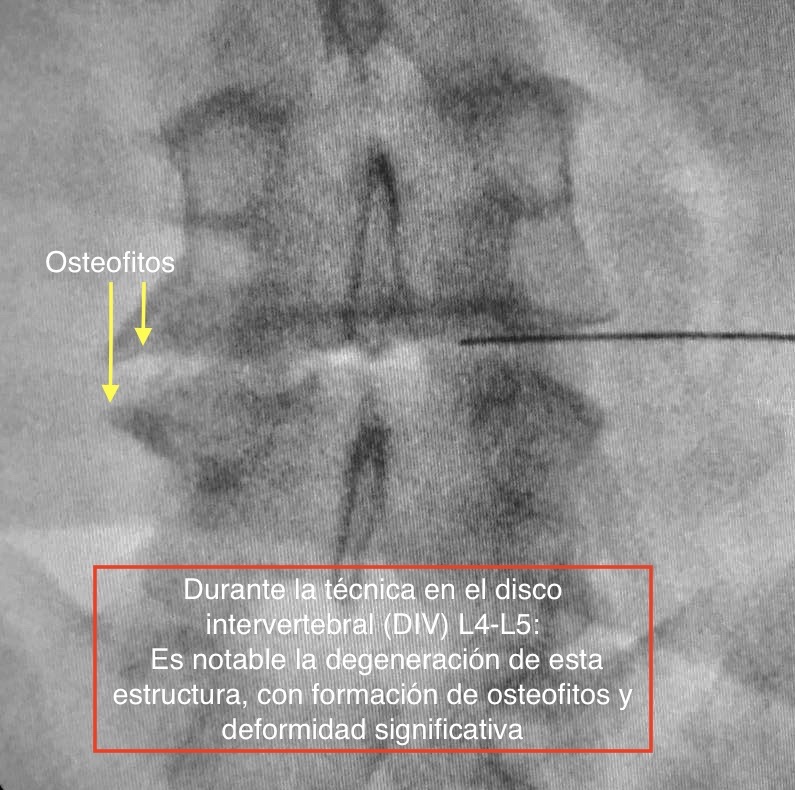

La TERAPIA REGENERATIVA NEUROESPINAL, desarrollada por el equipo de Neurocirugía de la Clínica del Remei (COT- Neurocirugía Remei) y dirigida por la Dra. Ivón González Valcárcel, es una Intervención novedosa y mínimamente invasiva exenta de reacciones adversas, avalada por evidencia científica, que utiliza la biotecnología. Nos brinda beneficios inmediatos en el control del DOLOR LUMBAR, así como ofrece efectividad en revertir la cascada degenerativa, con la consecuente REPARACIÓN y REGENERACIÓN del disco intervertebral y otros tejidos afectados.

Los factores de crecimiento plaquetarios son proteínas que se encuentran en nuestra propia sangre, ejerciendo importantes efectos biológicos. Mediante esta revolucionaria técnica, somos capaces de activarlos, concentrarlos e infiltrarlos con alta precisión en la zona dañada por la patología degenerativa. Así participarán directamente en la regulación del DOLOR y en la REGENERACIÓN, mediante la estimulación de funciones que dan lugar a la mejoría significativa o, inclusive, a la desaparición de los síntomas con rápido retorno a la actividad física cotidiana, con lo cual es una excelente alternativa a la cirugía convencional en muchos de los casos.